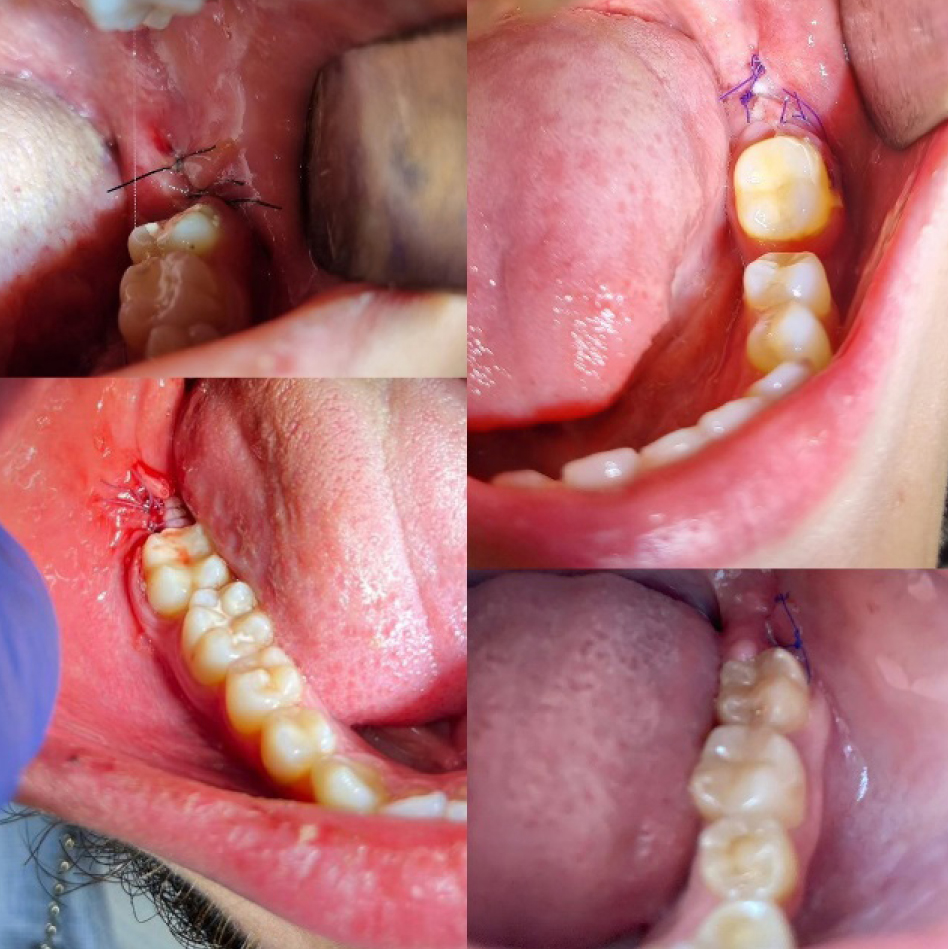

Всем пациентам проведено обследование, составлен план лечения. Операция атипичного удаления проводилась максимально щадящим способом с отслаиванием слизисто-надкостничного лоскута, трепанацией кортикальной пластинки костной и фрагментацией удаляемого зуба. Операционная рана заполнялась остеопластическим материалом, слизисто-надкостничный лоскут укладывался на место, накладывались узловые швы синтетическим, монофиламентым шовным материалом (рис. 4).

Рис. 4. Состояние лунок удаленных ретинированных зубов